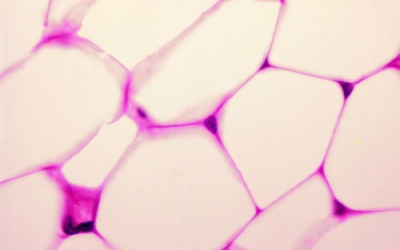

Biến các tế bào mỡ thành những “bộ máy” đốt cháy calori có lẽ là một ý tưởng tuyệt vời trong việc giảm cân nhưng nó không đến mức hoang tưởng như bạn nghĩ.